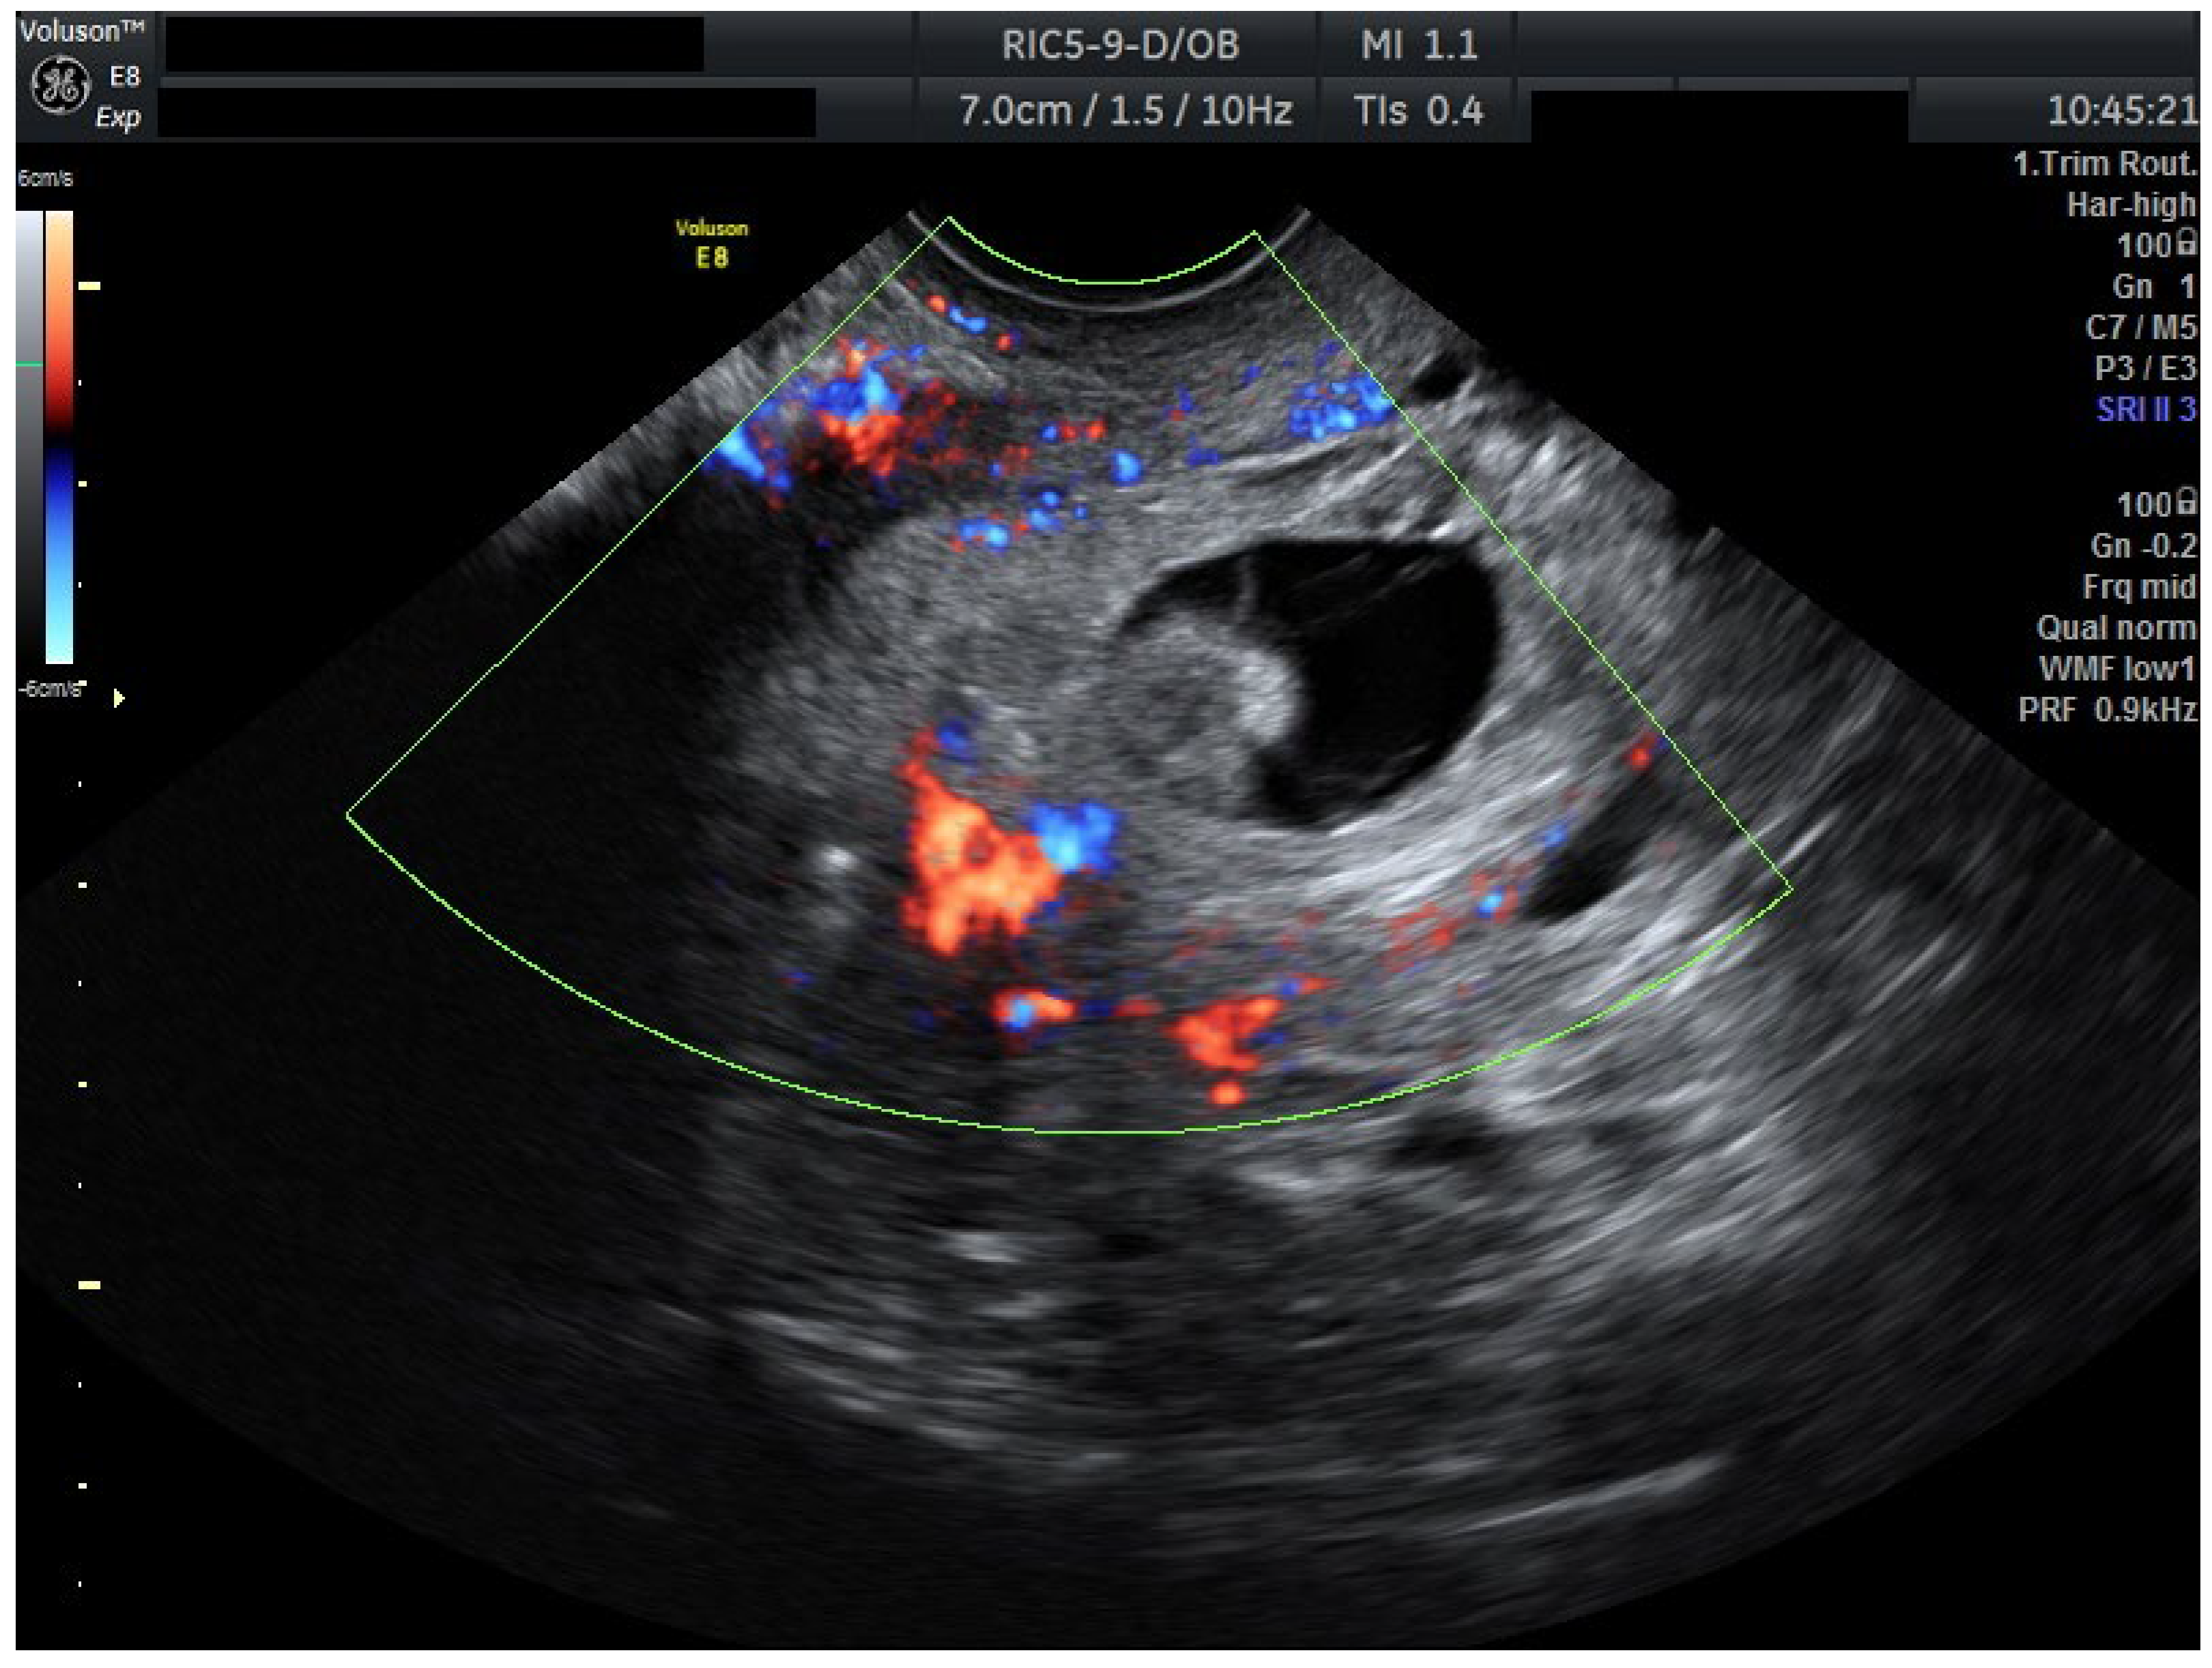

The patient’s recovery was uncomplicated under further uterotonic (misoprostol 0.2 mg every 8 h, intravaginally) to complete the expulsion of minimal residue and antibiotics (ceftriaxone f. 1 g once every 12 h, i.v.) (Figure 4). She was discharged in a stable condition, with β-hCG levels showing appropriate decline on dynamic follow-up.

Figure 4.

Timeline of clinical management in a case of HCP.

Day numbering is relative to the first mifepristone dose (Day 0). Doses: mifepristone 200 mg PO (Day 0) and 600 mg PO (Day 2); methotrexate (MTX) 100 mg IM (Day 4); misoprostol initiation (Day 12); suction curettage (Day 13). “Doppler surveillance (Days 6–11)” denotes serial TVUS showing progressive reduction in peritrophoblastic/cervical stromal flow and absent embryonic cardiac activity prior to instrumentation. Abbreviations: MTX, methotrexate; TVUS, transvaginal ultrasound; FHR, fetal heart rate; and IUP, intrauterine pregnancy. Anti-D prophylaxis and hemostasis adjuncts (e.g., Foley balloon, uterotonics) were available per institutional protocol.